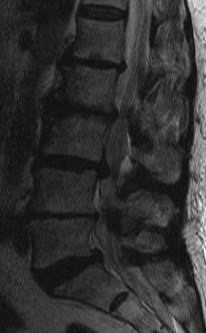

MRI

T2 Sagittal "MRI Myelogram"

Stenosis typically at disc level either due to disc or facets

1. Central Canal

- bulging of annulus posterior

- facet osteophytes posterolateral

- hypertrophied ligamentum flavum posterolateral

2. Lateral Recess

- facet subluxation & osteophytes + hypertrophied ligamentum flavum